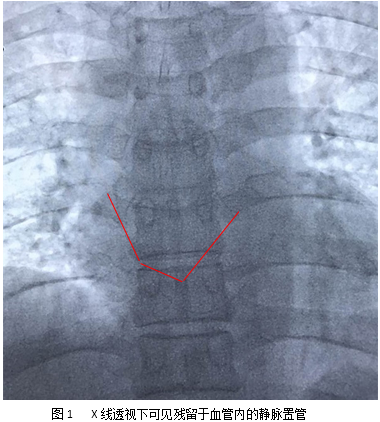

经过充分的术前讨论和准备后,在麻醉科同仁的配合下,放射科介入团队叶斌、张声旺、吴作为、罗雪梅、何海波于介入室行心脏异物取出术。术中可见患者心脏内断裂导管一端紧贴心脏前壁、另一端嵌顿于心大静脉,抓捕器无法直接接触抓捕,手术团队冷静思考后决定采用非常规猪尾导管套取异物移位,再采用抓捕器抓捕的方法实施介入手术。患者术中心率极不稳定,手术团队沉着冷静,凭借精湛的技术和高超的胆识,经过近2个小时的努力,最终将心脏内异物导管成功取出。